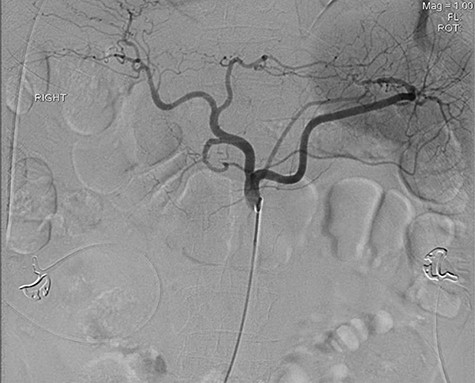

A 56-year-old African American male presented in 2015 with abdominal pain, with associated melena and hematochezia. The patient has a history of chronic back pain for which he takes 600 mg ibuprofen daily, alcohol abuse, tobacco use and a previous GI bleed in 2011, which necessitated 6 units (U) of packed red blood cells (PRBCs) and emergency therapeutic endoscopy. The patient was found to be hypotensive to 76/56 mm Hg, and hemoglobin (Hgb) was found to be 9.4 g/dl, from a previous baseline of 10.6 g/dl. His rectal examination was guaiac positive. A repeat Hgb was found to be 6.5 g/dl. The patient was given 3 U of PRBC and an emergency endoscopy was performed. On endoscopy, the patient was found to have a 6 cm gastric ulcer with an associated vessel underneath of a large clot. Due to the high risk nature of the bleed, it was felt by the gastroenterologist that the patient should undergo an endovascular angioembolization (Fig. 1). The patient was brought to the Interventional Radiology Suite for the procedure. The patient’s right common femoral artery was accessed and the celiac trunk was selected. A subselective common hepatic arteriogram was performed, which demonstrated active extravasation arising from the proximal aspect of the GDA. The GDA was then coil embolized both proximal and distal to the site of bleeding using five microcoils. Repeat arteriogram demonstrated no further opacification of the GDA and no further extravasation (Fig. 2).

Demonstrating active extravasation of the GDA during a subselective GDA arteriogram